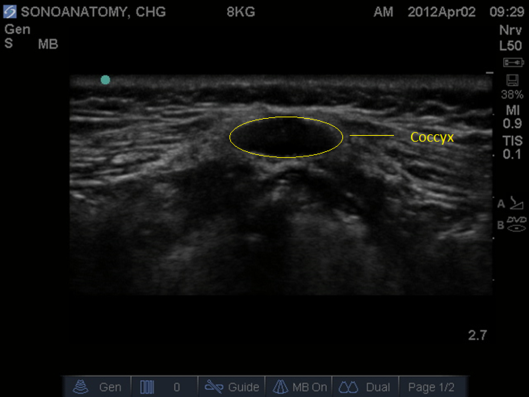

Fig 2. Ultrasound Probe in Midline Transverse position over the coccyx.

C – sacral cornu, white asterisk sacrococcygeal membrane.

- Prior to performing the caudal a ‘Mapping’ or ‘Scout’ scan is performed to assess the position of the dural sac in relation to the sacrococcygeal membrane. The angle of needle/cannula insertion can be observed. See Figs 1-7.